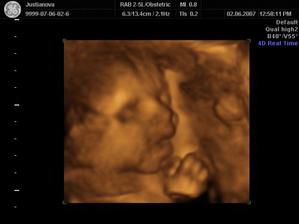

Kubíček, jak jde čas...

Tak už jsem tady, narodil jsem se 19.8.2007 ve 13,25. Měřil jsem 48cm a vážil 3150gramů a jmenuji se Kubíček a tak jde čas...